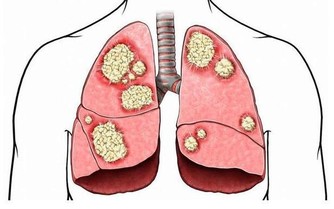

1.腦血管病:

最常見的有多發性腦梗死性癡呆,是由於一系列多次的輕微腦缺血發作,多次積累造成腦實質性梗死所引起。此外,還有皮質下血管性癡呆、急性發作性腦血管性癡呆,可以在一系列腦出血、腦栓塞引起的腦卒中之後迅速發展成癡呆,少數也可由一次大面積的腦梗死引起。總之,腦血管病也是老年癡呆較為常見的病因。